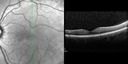

VMT-3-2.jpg

Macular Pucker489 viewsOCT scan of MP

VMT-1-2.jpg

Macular Pucker432 viewsOCT scan of MP

VMT-2-2.jpg

Macular Pucker429 viewsOCT scan of MP